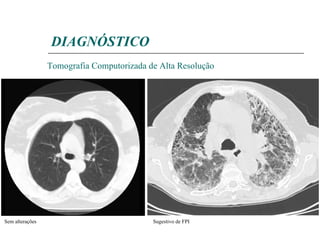

DIAGNÓSTICO TOMOGRAFIA COMPUTORIZADA ALTA RESOLUÇÃO Infiltrado reticular difuso de distribuição sub-pleural e basal Padrão em favo de mel História clínica Exame físico Testes laboratoriais Provas de Função Respiratória Electrocardiograma Ecocardiograma Radiografia Tórax Tomografia Computorizada de Alta Resolução Broncofibroscopia Biópsia pulmonar Extensão atingida Selecção de local de biópsia Técnica de eleição para follow up

Tomografia Computorizada de Alta Resolução Sugestivo de FPI Sem alterações DIAGNÓSTICO

DIAGNÓSTICO TOMOGRAFIA COMPUTORIZADAALTA RESOLUÇÃO Infiltrado reticular difuso de distribuição sub-pleural e basal Padrão em favo de mel História clínica Exame físico Testes laboratoriais Provas de Função Respiratória Electrocardiograma Ecocardiograma Radiografia Tórax Tomografia Computorizada de Alta Resolução Broncofibroscopia Biópsia pulmonar Extensão atingida Selecção de local de biópsia Técnica de eleição para follow up

Tomografia Computorizada deAlta Resolução Sugestivo de FPI Sem alterações DIAGNÓSTICO